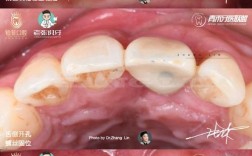

(图片来源网络,侵删)- 挂号(口腔种植科或相关亚专业如口腔颌面外科、口腔修复科,具体看你的情况)。

(图片来源网络,侵删)- 这是种植体与牙槽骨紧密结合的关键时期,称为“骨结合”。